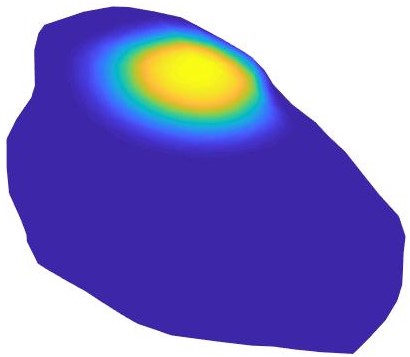

We have applied our proposed procedure to the solution of equations (40)-(42) with the parameters shown in Table 2. These equations are solved on the epicardium, which is the outermost surface membrane of the heart and which is shown in Figure 7(a). We also show the points used for the numerical solution of the problem. These points have been obtained from a computerized tomography (CT) of a real patient [8]. Therefore, it is a realistic model in which we do not have information neither on the normal vectors nor on the curvature of the surface. We consider

| (43) |

shown in Figure 7(b). Here, denotes the Heavisade function, the time when the stimulus ends, the position where the stimulus is applied, and its spatial width.

We use the same method that in the previous example for temporal integration. The solution shows the propagation of the electric excitation along the membrane. For instance, Figure 7 (c) shows the transmembrane current 50 ms after the stimulus ends. The tissue goes from a resting to an excited state. Finally, the membrane returns to the resting state awaiting for the next stimulus. This behavior can be observed in Figure 7 (d), where we show the evolution with time of the transmembrane voltage and the gate variable at the point in Figure 7 (c). As we can see, the cardiac tissue experiences the different stages of a heartbeat corresponding to those shown in [25].